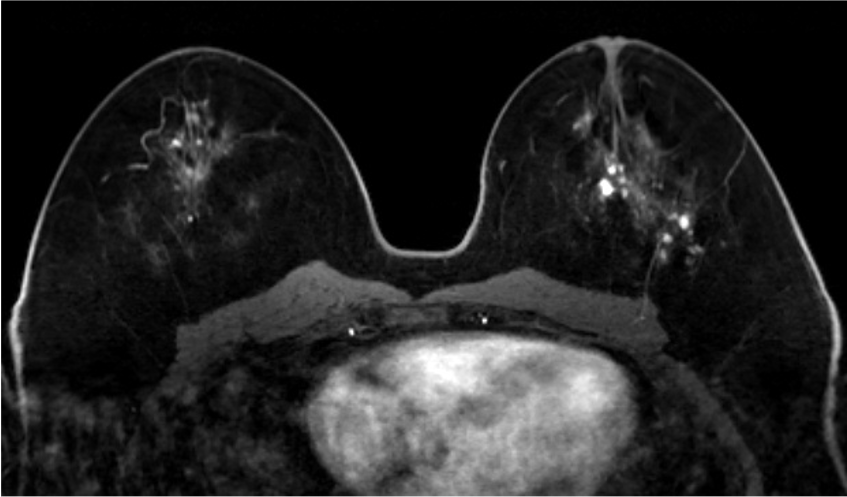

4. ダイナミックMRI (造影前 早期相 遅延相)

乳腺散在性の乳房であるが、造影早期から背景乳腺の大部分が造影されており、BPEはmarkedである。DCISの病変(矢印)は、clumped、segmental distributionの腫瘤非形成性病変(Non-mass enhancement)を示しているが、BPEが強く、広がり診断が困難である。